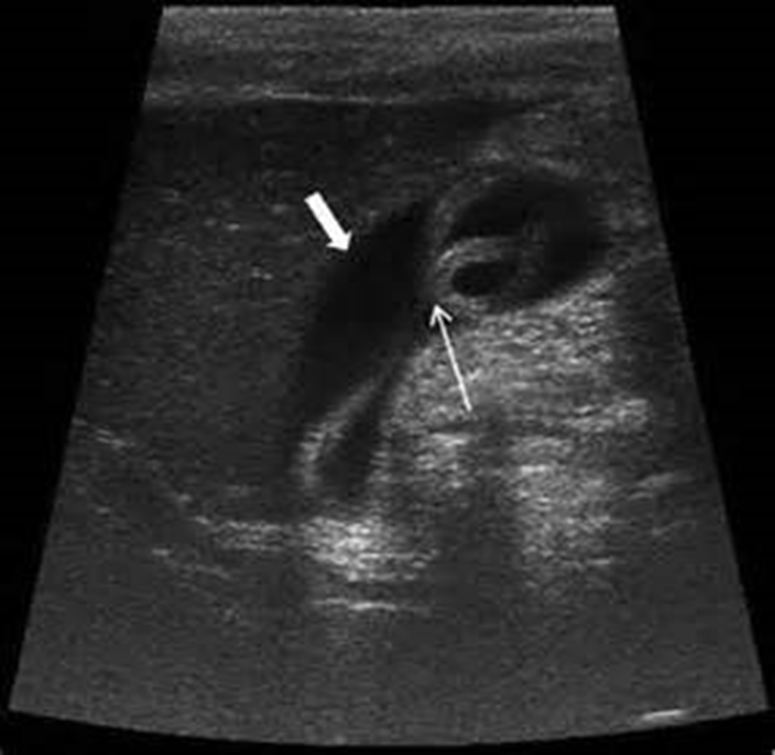

# 1 Pt. c/o RUQ pain, this image looked the same in both supine and LLD positions. Name the pathology

Cholesterolosis showing multiple cholesterol polyps

HINT: NO FEVER

Cholelithiasis

sludge

Adenomyomatosis

artifact: comet tail

porcelain gallbladder

Adenocarcinoma